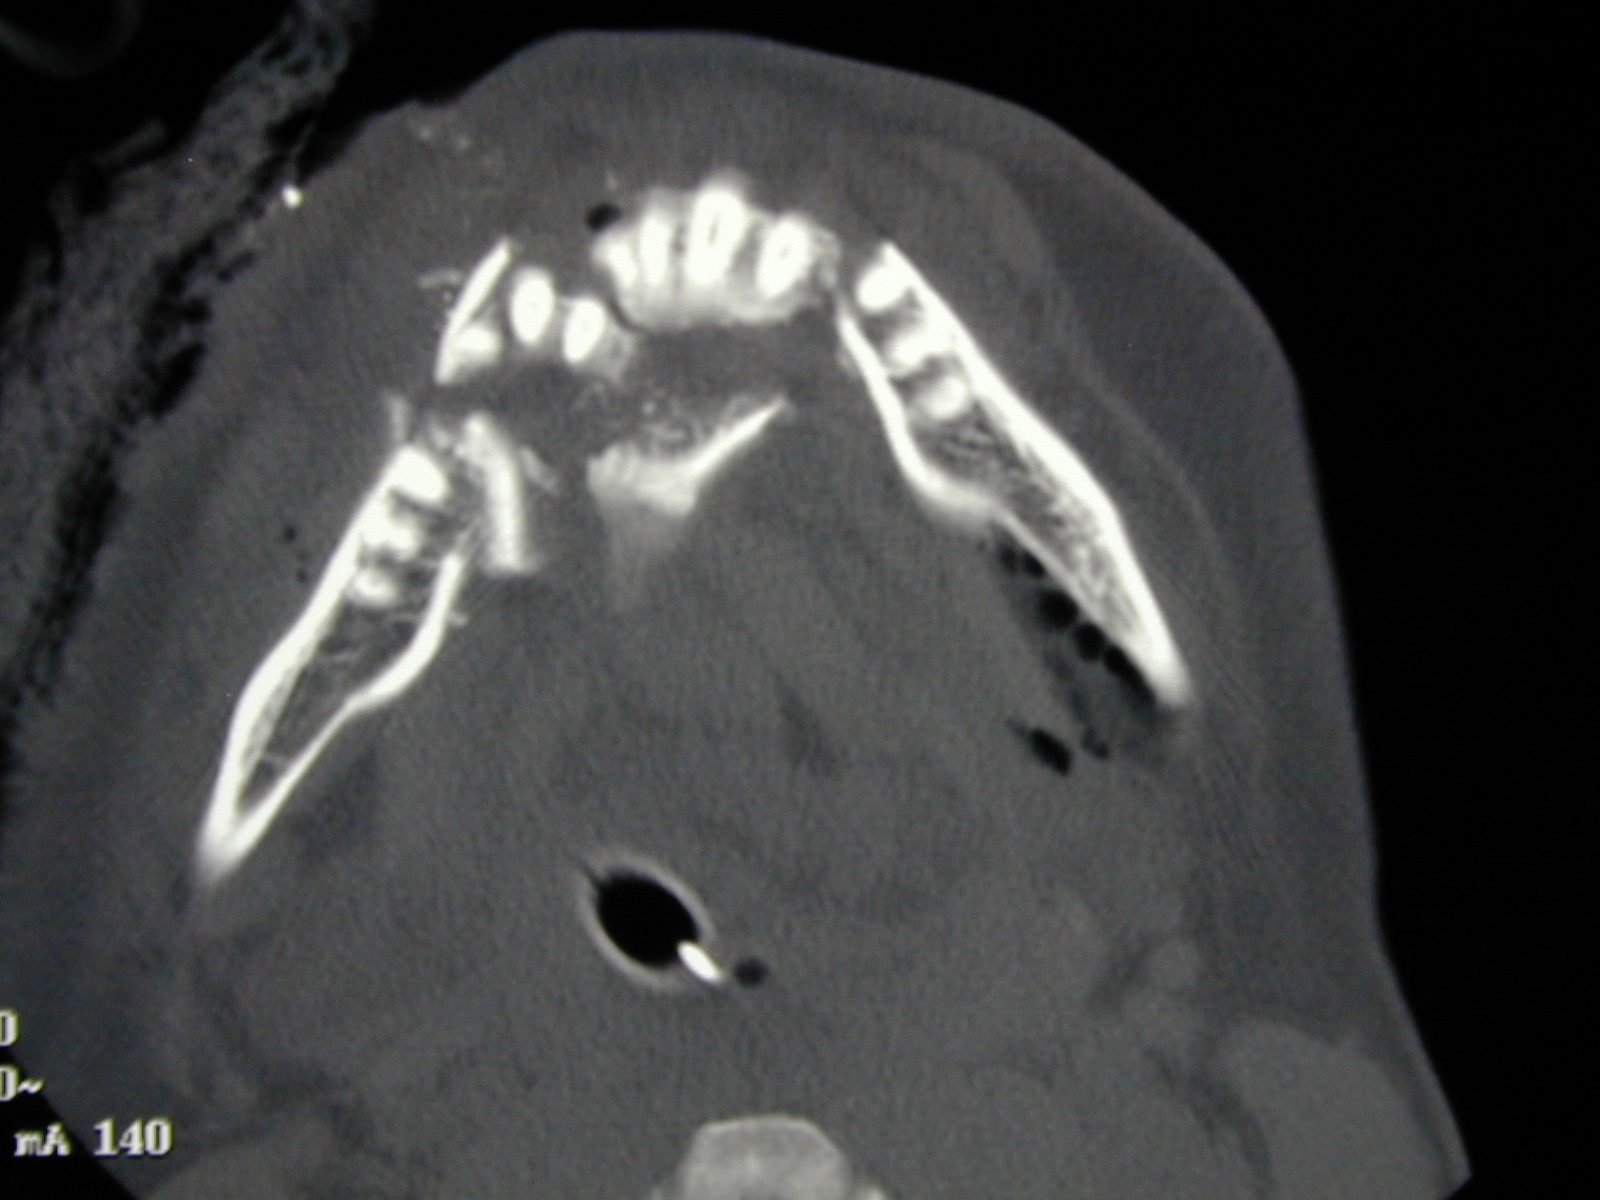

Other applications include a range of bone lesions such as cystic lesions of the jaws (Figure 11).

Figure 11: A benign cystic lesion of the mandible; comparison of a conventional two-dimensional X-ray image (DPT; top) and a CT scan (bottom).